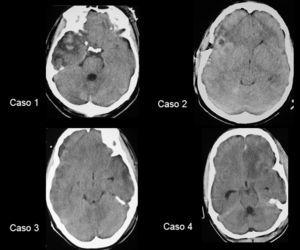

El caso 1 se trata de un hombre de 41 años de edad que ingresa en coma Glasgow 7, con lesión difusa tipo II en la TC craneal (fig. 1); el caso 2 un hombre de 20 años de edad ingresado en coma Glasgow 7 con lesión difusa tipo II en la TC craneal (fig. 1); el caso 3 una mujer de 20 años de edad ingresada en coma Glasgow 8 y con lesión difusa tipo III en la TC craneal (fig. 1), y el caso 4 un hombre de 23 años de edad que ingresa en coma Glasgow 3, intoxicación etílica y con lesión difusa tipo III en la TC craneal (fig. 1).

Figura 1. Tomografía computarizada craneal de los 4 pacientes realizada al ingreso.